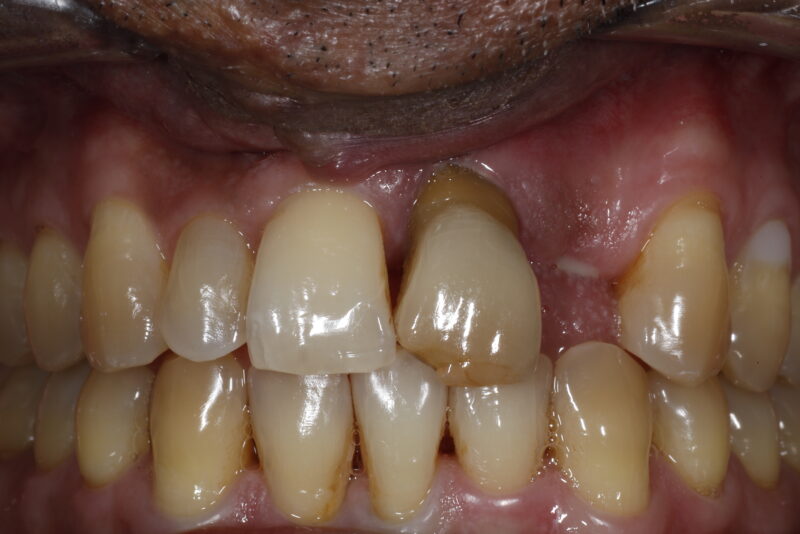

The destructive consequences of periodontal disease. We have many great ways to help patients take their health back and replace their teeth but it’s so much better (and much less expensive) to just take care of your own teeth and form healthy habits from the beginning. Together as a profession, let’s please make sure that we’re properly…